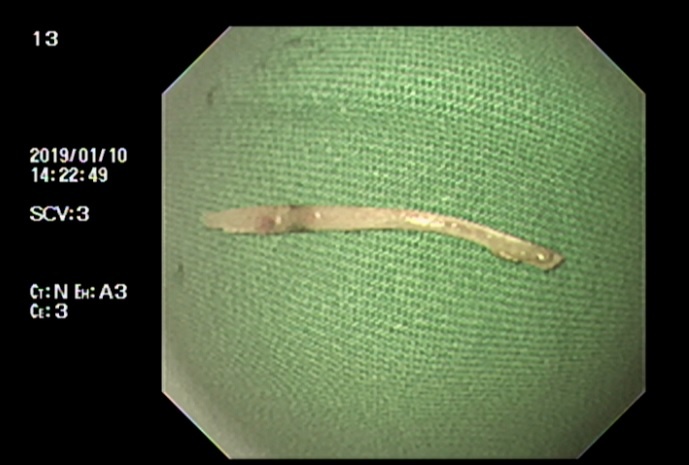

| Mảnh xương sau khi được gắp ra từ thực quản bệnh nhân. Ảnh: BVCC |

Các bác sĩ đã chỉ định nội soi dạ dày, kết quả phát hiện dị vật cắm sâu vào thực quản, gây hai ổ áp-xe chảy nhiều dịch mủ, cách cung răng trên khoảng 20 cm. Bệnh nhân T. được tiến hành gắp dị vật, làm sạch ổ mủ, cầm máu. Dị vật là mảnh xương gà có hai đầu sắc nhọn dài khoảng 4 cm.